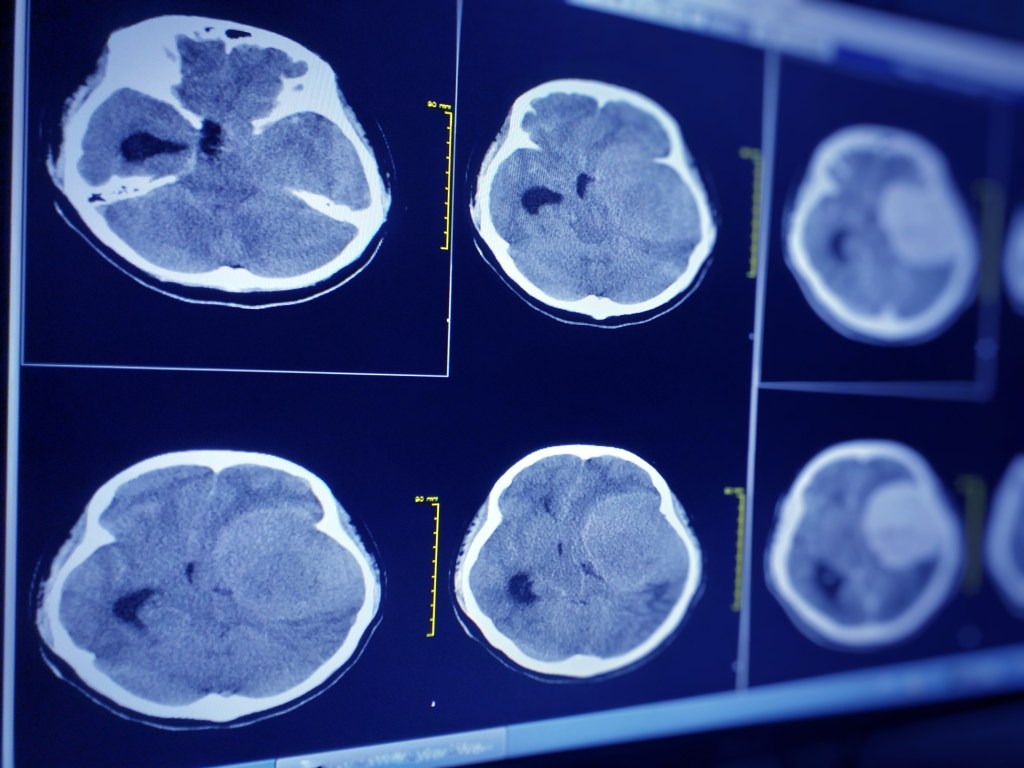

As defined by the National Institute of Neurological Disorders and Stroke (NIH), ‘a traumatic brain injury (TBI) refers to a brain injury that is caused by an outside source.’ The symptoms vary from person to person but commonly include loss of consciousness, headache, vision problems, and other neurological problems. TBIs are typically diagnosed by imaging tests like CT or MRI scans and are categorized into different severity levels: mild, moderate, and severe. In my case, I had a severe TBI.

When I was first hospitalized, I had hematomas (bleeding in and around the brain). The doctors had to shave the right side of my head and insert a device to relieve the swelling and bleeding. Later, I was diagnosed with neuropathy (nerve damage), GERD (acid reflux), and chronic headaches/migraines. I was prescribed gabapentin for neuropathy, but the side effects were unbearable, so I stopped taking it. Recently, I’ve started back on medication for my acid reflux because it was affecting my ability to eat and drink anything acidic. Thankfully, I’m feeling better physically now.

CT Brain seven cm. diameter hyperdensity mass with lobulated surface at extra-axial lateral to lt frontal and temporal lobe. Free photo. (n.d.). vecteezy.com. https://www.vecteezy.com/photo/15763194-ct-brain-seven-cm-diameter-hyperdensity-mass-with-lobulated-surface-at-extra-axial-lateral-to-lt-frontal-and-temporal-lobe